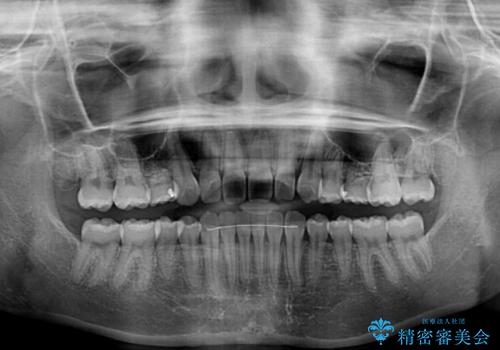

ディープバイトをインビザライン矯正で改善

- 前歯のデコボコと強い咬みしめを気にして来院された患者様です。

インビザラインを用いて、前歯の叢生を解消するとともに、ディープバイトを改善していくこととしました。

上顎に乳歯が左右1本ずつ残っていたため、若干咬み合わせに不具合が残りましたが、強い咬合力の原因であったディープバイトをしっかりと改善することができました。